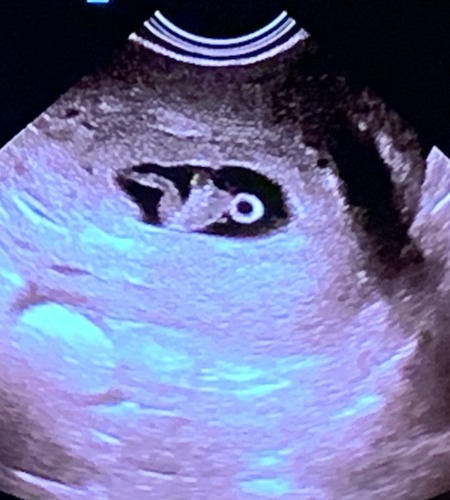

9+2 inwendig van rugaanzicht. Baby was lekker veel met zijn armpjes en beentjes aan het bewegen, zo leuk om te zien 🥰